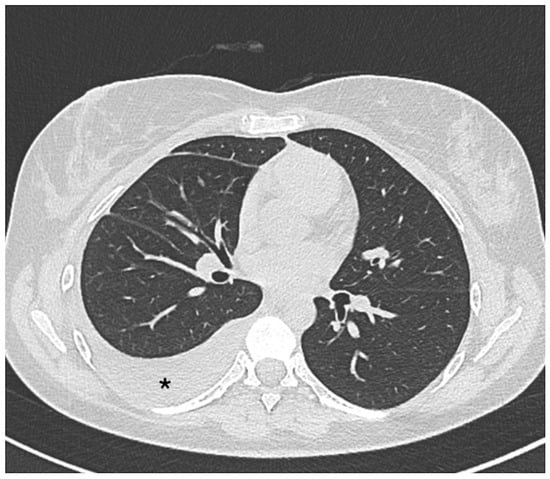

A chest X-ray showing effusion and/or thickening is usually sufficient to establish a diagnosis. In addition, it is crucial to rule out other potential causes of pleural inflammation that can occur alongside SLE, including infections, pulmonary embolism, cancers, heart failure, and pericarditis [29]. The pleural effusion can also be visualized on a chest CT scan (Figure 1).

Figure 1.

Axial non-contrast thorax computed tomography scan in a patient with systemic lupus erythematosus. The exam revealed abnormal accumulations of fluid within the pleural space (asterisk).